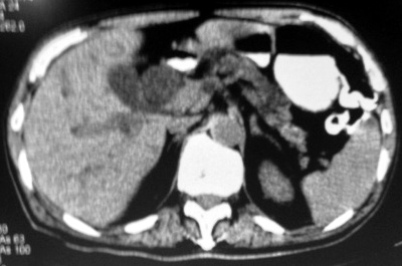

The patient had been on simvastatin the last five years, the rest of his medical history was negative. There was no relevant family or social history. In his physical examination, the patient was pale with no evidence of jaundice. The patient lost 10 kg during the past year without dieting and was suffering from symptoms of depression during the same period. An abdominal examination revealed an indirect left inguinal hernia. A rectal examination was normal. Investigations confirmed low haemoglobin 8.3 g/dL and haematocrit 25%.The rest of the biochemical examinations were normal. In the tumour markers, only the CA (carbohydrate antigen) 19-9 was elevated with a value of 169.67 U/mL. An abdominal ultrasound and colonoscopy showed non-pathological results. The gastroscopy revealed a large tumour of the ampulla of Vater (Figure 1), while the histology was positive for malignant cells with sarcomatous characters and frequent mitotic figures (>40/10 high power fields). The computed tomography scan demonstrated a large mass of the ampulla of Vater, causing obstruction and dilatation of the common bile duct, the intrahepatic and the pancreatic duct (Figure 2). The magnetic resonance revealed a large mass of the uncinate process of the pancreas of 4.7x4.5 cm and the dilatation of the intrahepatic bile ducts, common bile duct and pancreatic duct with no invasion of the superior mesenteric vessels or the portal vein and no metastasis.

Figure 2. CT of the abdomen which shows a mass at the ampulla of Vater with dilated common bile duct, pancreatic duct and intrahepatic ducts. |